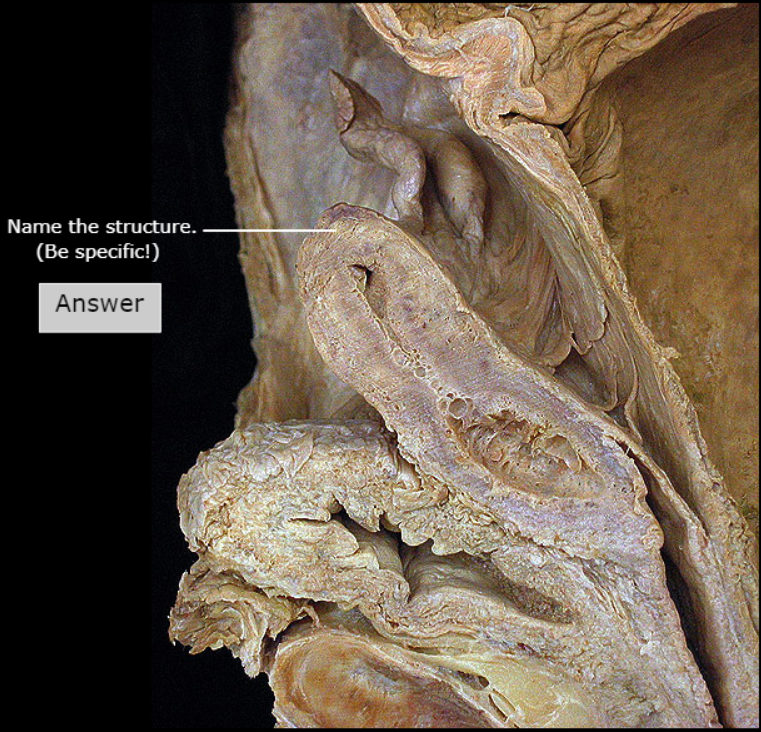

Fundus of Uterus